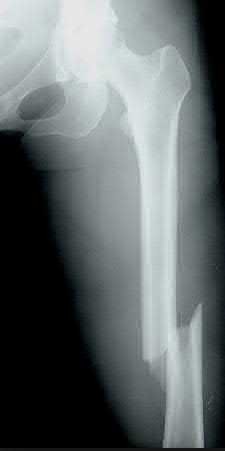

A 15-year-old boy presents with a permeative lytic lesion in the femoral diaphysis with aggressive periosteal reaction ('onion skinning'). Biopsy reveals uniform small round blue cells. Cytogenetic analysis of this tumor will most likely demonstrate which of the following translocations?

Explanation

The clinical and radiographic description is classic for Ewing sarcoma. The characteristic cytogenetic abnormality is a balanced translocation t(11;22)(q24;q12), which fuses the EWS gene on chromosome 22 with the FLI1 gene on chromosome 11. This is seen in approximately 85-90% of Ewing sarcomas. t(9;22) is the Philadelphia chromosome (CML), t(X;18) is seen in synovial sarcoma, t(2;13) in alveolar rhabdomyosarcoma, and t(12;16) in myxoid liposarcoma.